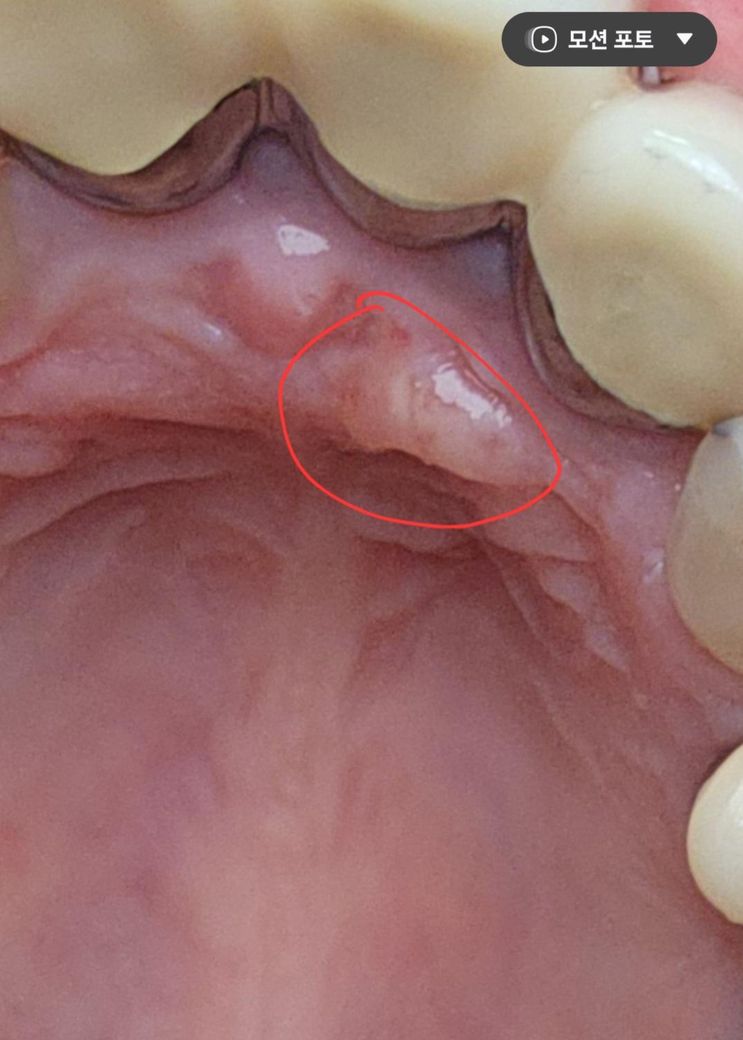

잇몸 입천장쪽에 생긴 이것은 무엇일까요~?

잇몸 입천장쪽에 생긴 이런게 생겼습니다.

생긴지는 한달정도 된것 같은데 혹시 무엇일까요~?

입천장이 자극을 받아서 생긴 염증일수도 잇지만 치아때문에 생긴 염증일수도 잇으니 치과에 가셔서 일단 치과에 가셔서 엑스레이를 찍어보시는게 좋을것같습니다

사진상 농양이 생긴 것으로 보입니다. 씌운 치아가 신경치료가 되어 있다면 재신경치료, 신경치료가 안되어 있다면 신경치료가 필요할 수 있겠습니다